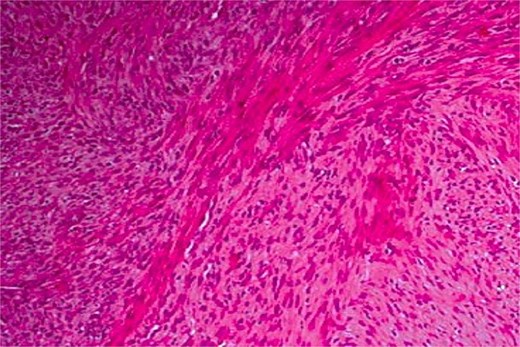

Haematoxylin and eosin stain at ×100 magnification showing a leiomyosarcoma composed of perpendicularly oriented fascicles of spindle-shaped cells.

Histopathologically, leiomyosarcoma is characterized by spindle-shaped cells with eosinophilic cytoplasm and elongated nuclei in fascicular patterns. Immunohistochemistry, including desmin and smooth muscle actin, helps differentiate it from other spindle-cell neoplasms [4], with calponin improving diagnostic specificity [5].